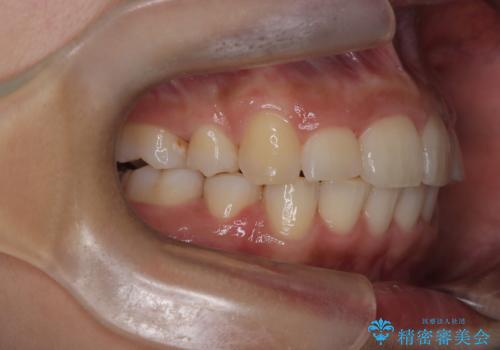

- 前歯の凸凹を主訴に来院されました。

抜歯を行い、ワイヤー矯正にて治療を行いました。

凸凹もなくなり、歯磨きもしやすくなったと喜んでいただきました。

CTにて骨を確認し、側切歯の歯根をこれ以上頬側に出せないことを確認しています。